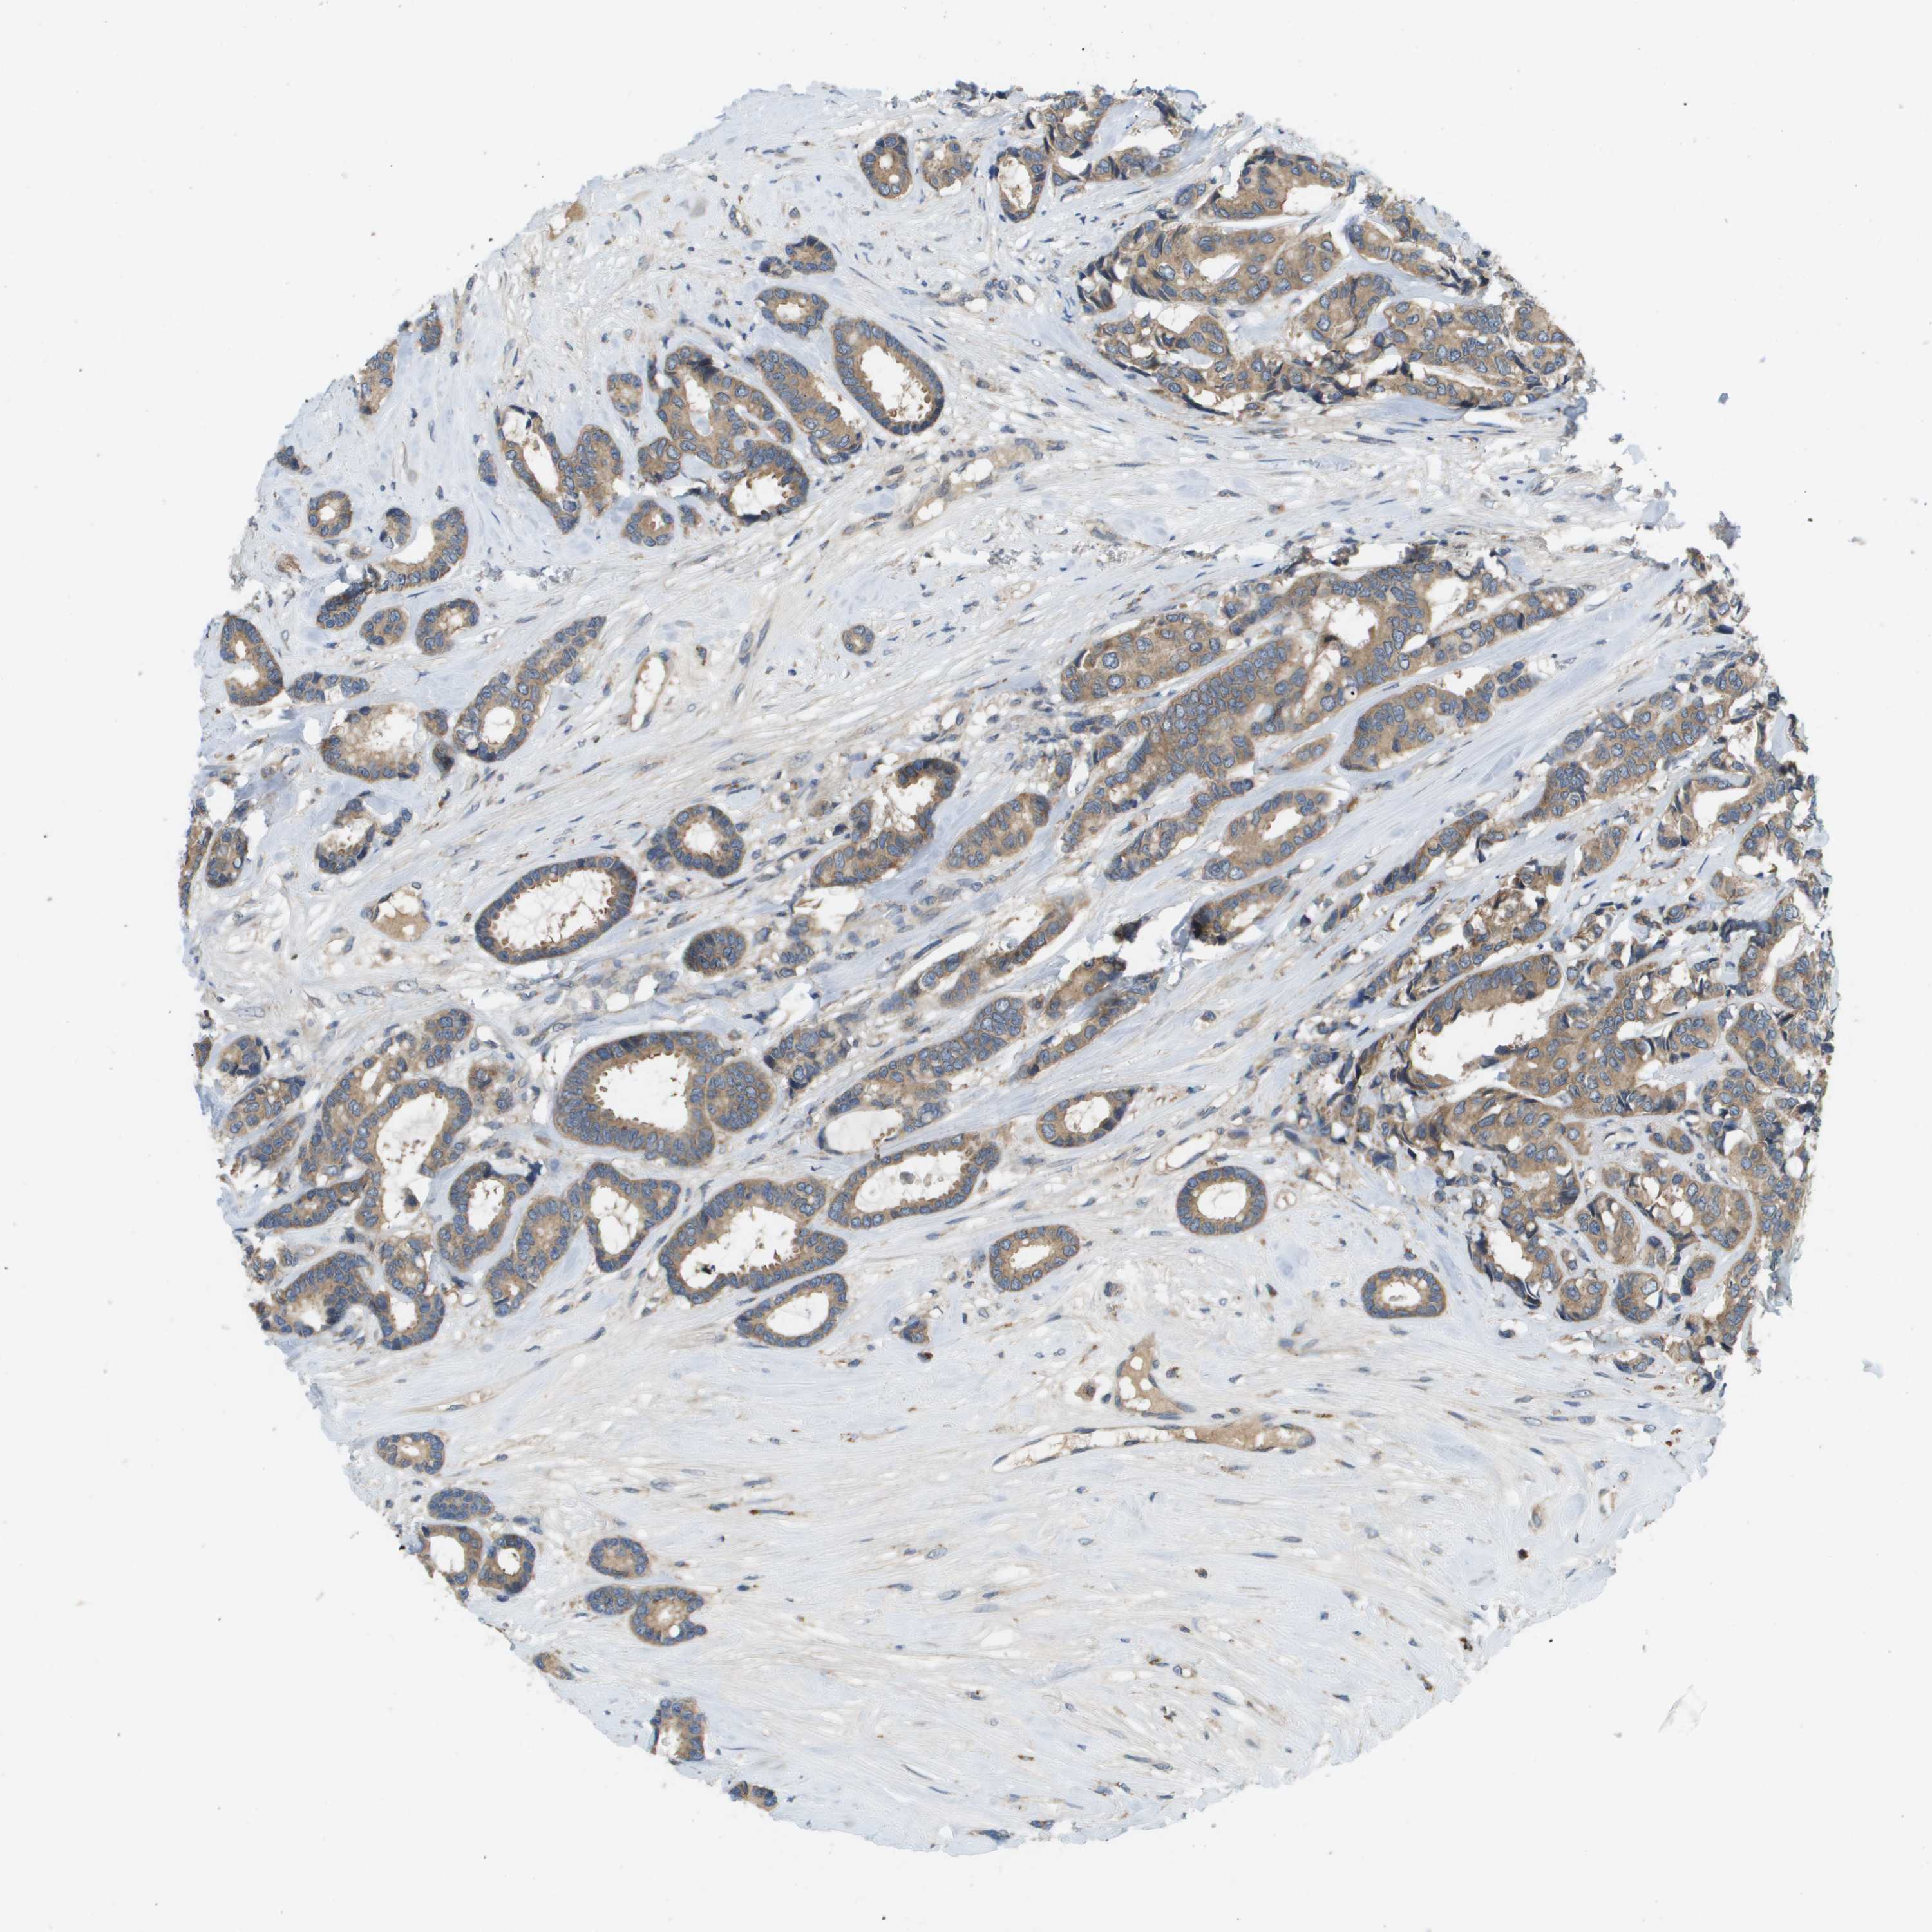

CANCER BREAST CANCER Show tissue menu

BRCA TCGA BRCA VALIDATION PROTEIN EXPRESSION